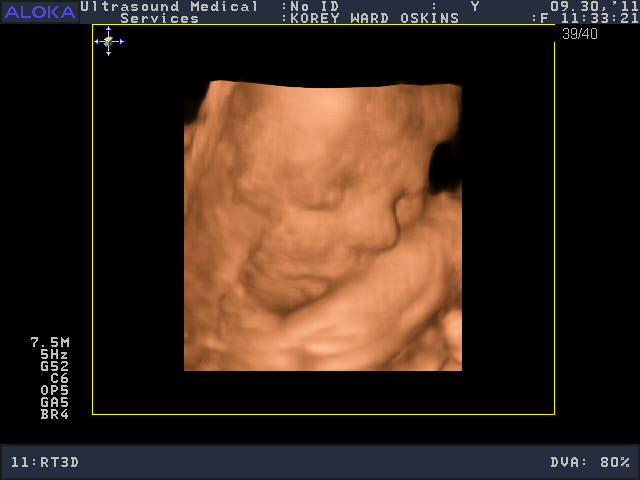

He was a very stubborn baby, so it was really kind of nerve-wracking at first thinking we might not get a single good picture. His face was squished up against the placenta and he wouldn’t budge. You’ll see that in the pictures below; it looks like an enveloping cloud or a scallop shell. Finally he moved a bit and we got some glimpses of his face. We saw him make some facial expressions, wiggle his fingers, and move his mouth around. We were curious to see whose nose he would have, and in some pictures, it looks like he has Josh’s, in others, mine.

So who do you think he looks like?

He is sooooo cute! Personally, I think he looks like ME.